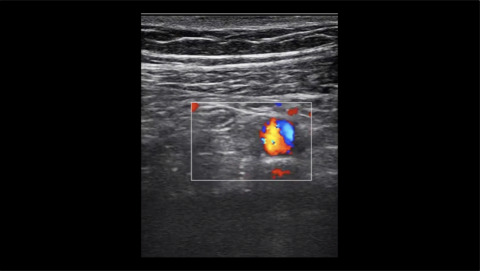

Ultrasound of Target Sign in Appendicitis

Dr. Avila demonstrates the target sign on ultrasound seen in appendicitis.